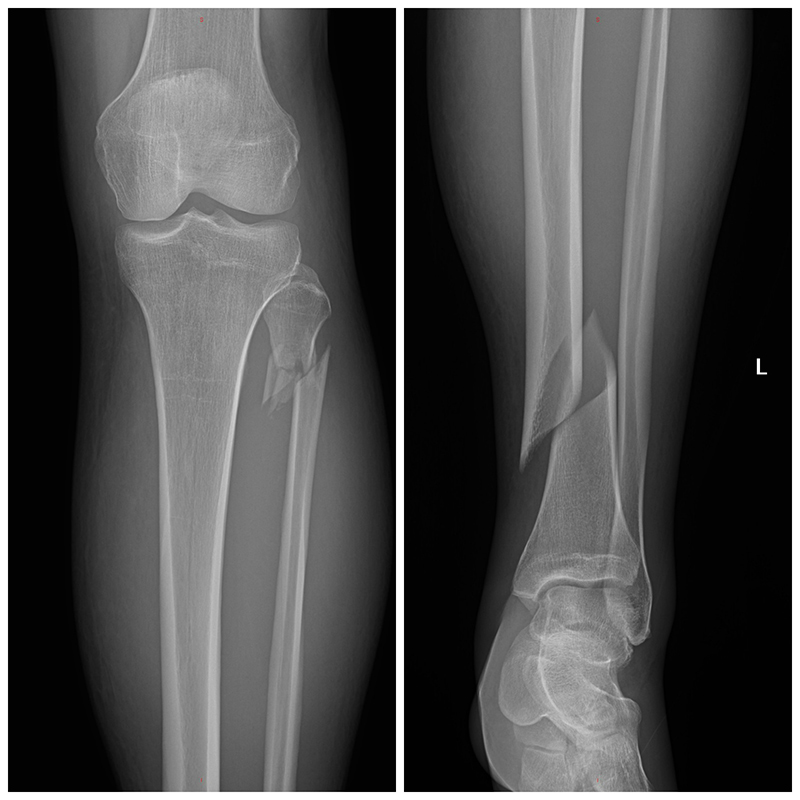

The shoulder seemed to work, my neck was fine, and my ankle felt sprained. “Okay, great.” I thought, “I’m going to walk away.” Then I stood and excruciating pain shot up my leg. Falling to the ground, I looked down to see that my left ankle was dangling. I turned my knee to the right but the ankle didn’t follow, only pain.

After a few days I got a propeller plane to take me to Roatan, and a medevac flight from there to a hospital in Miami, where I had surgery to repair a broken tibia/fibula. After three more nights in the hospital I caught a flight back home to Washington State.